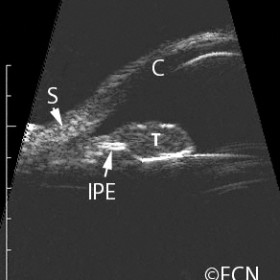

Iris Melanoma

Iris Melanoma - 20 MHz B-scan demonstrates how the tumor (T) can break through and destroy the hyperechoic iris pigment epithelium (IPE).